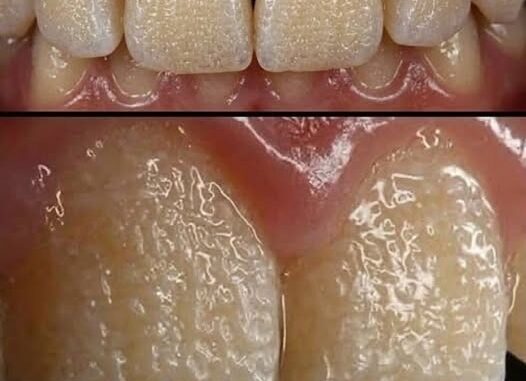

One possible explanation is Amelogenesis Imperfecta (AI), a genetic condition that affects enamel—the hard outer layer that protects teeth. When enamel doesn’t form properly, teeth can appear discolored, fragile, pitted, or unusually small.

Enamel is the hardest substance in the human body, created by specialized cells during early development. In AI, genetic mutations disrupt this process, leading to enamel that may be too thin, too soft, or poorly mineralized.

There are several types of AI. In hypoplastic AI, enamel is thin but hard. In hypomaturation AI, enamel forms at normal thickness but is softer than usual. Hypocalcified AI involves enamel that is fragile and wears away quickly. The condition can run in families.